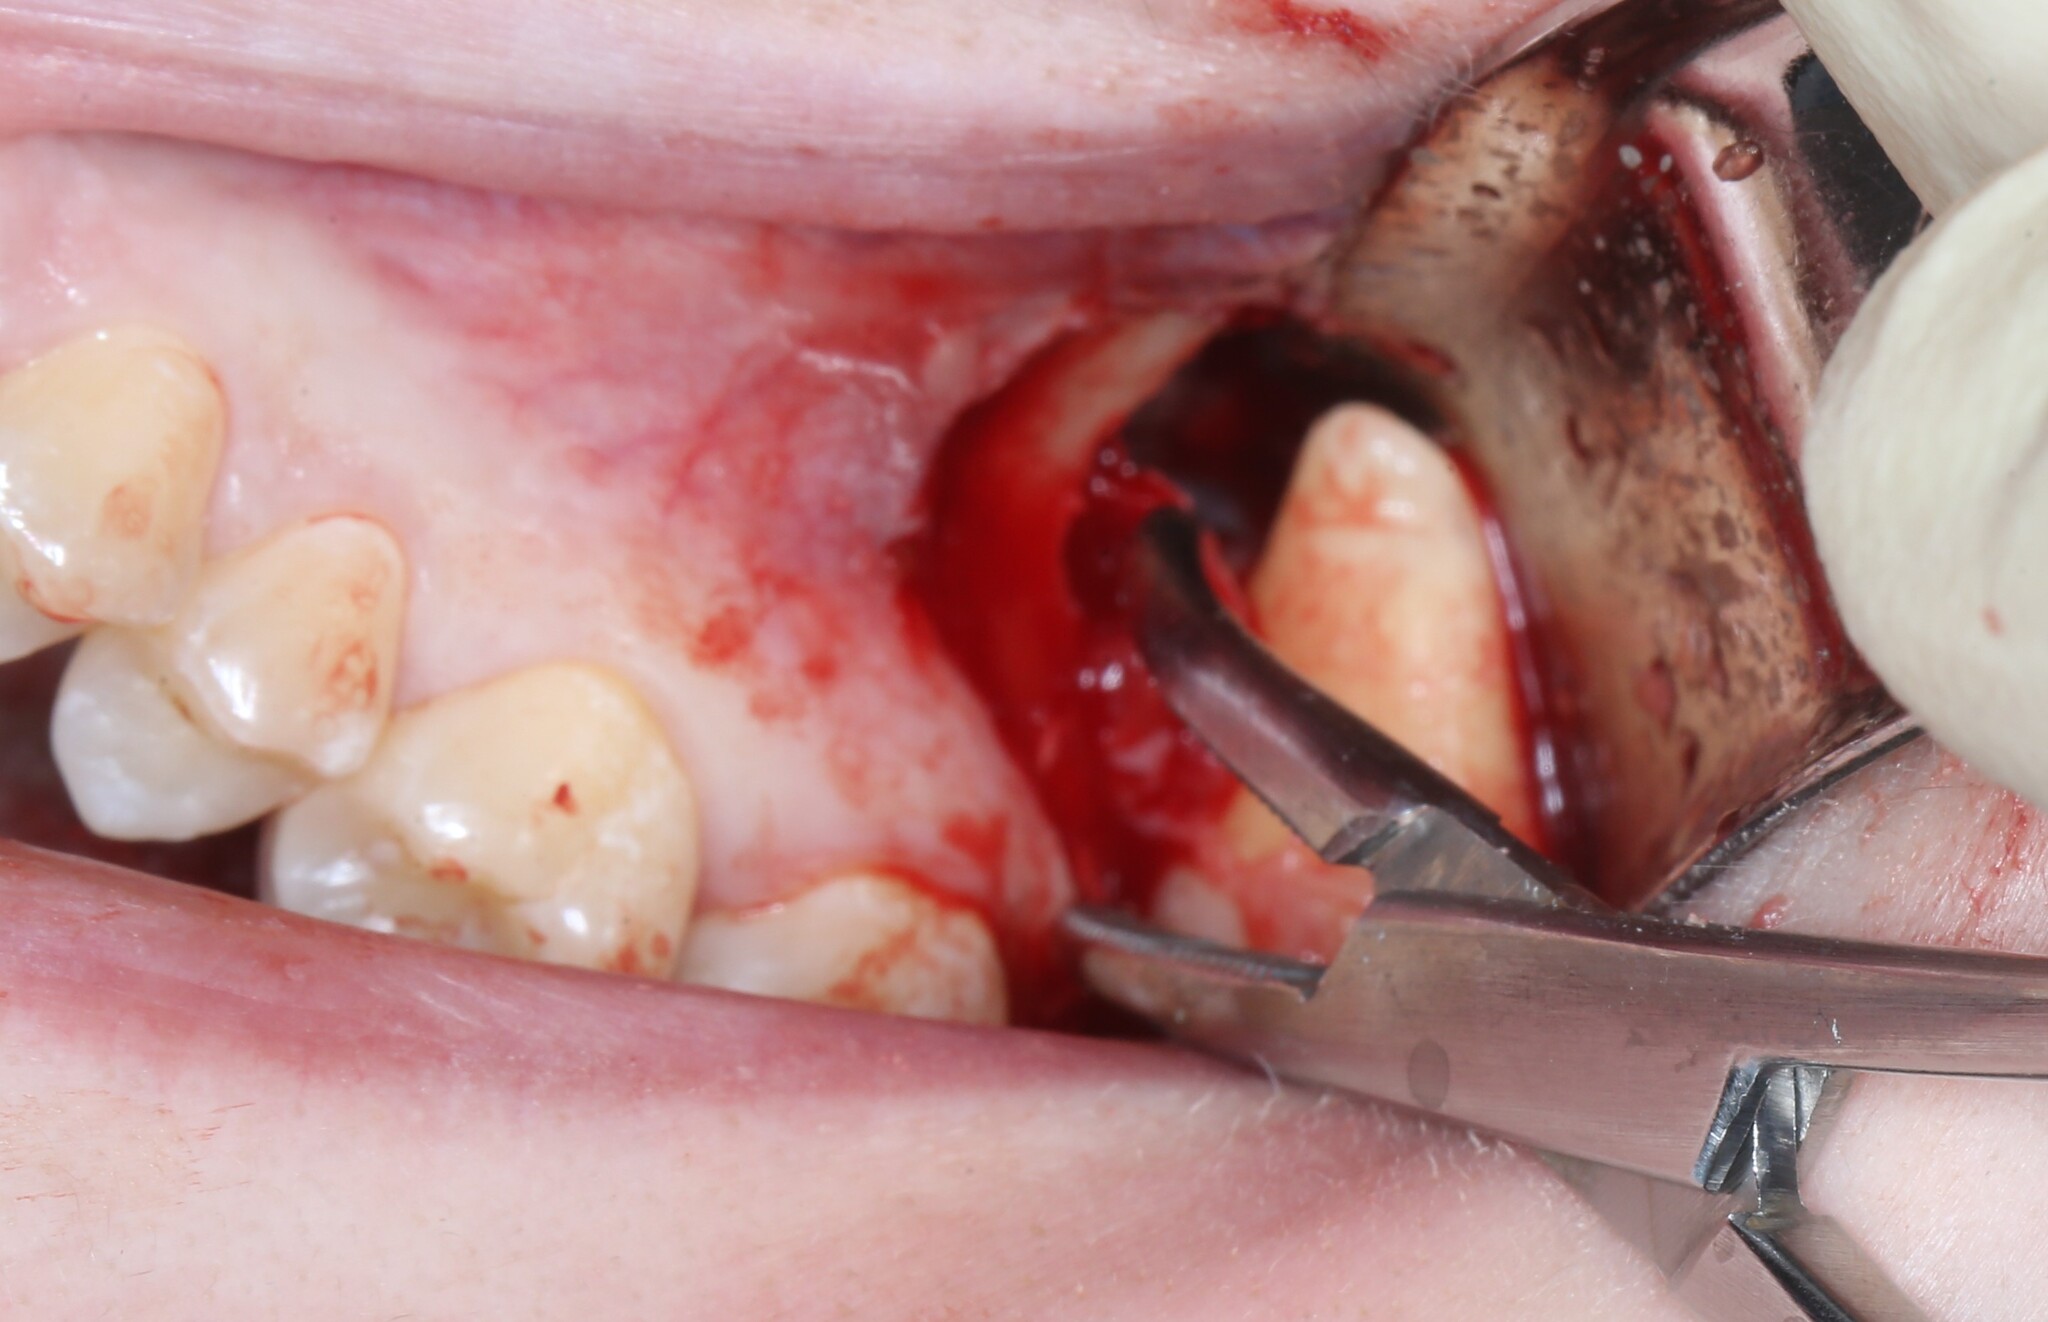

Добрался до кости и при помощи специального прямого наконечника и шаровидного бора сделал окошко в проекции верхнечелюстной пазухи и удаляемого зуба мудрости:

Вооон там сверху уже можно увидеть жевательную поверхность зуба (белого цвета).

Понял, что окошко маловато. Немного «расширяемся»:

и начинаем подтягивать зуб при помощи элеватора:

Вот и он «красавчик». Берем зажим и хватаем эту мразоту за хвост, точнее за фолликул и извлекаем: